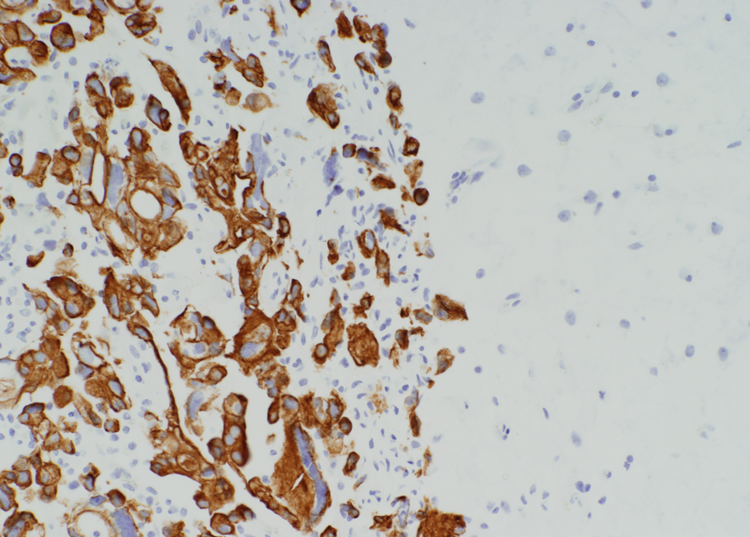

Brain met

cytokeratin stain

Stain for brain met

Cytokeratin